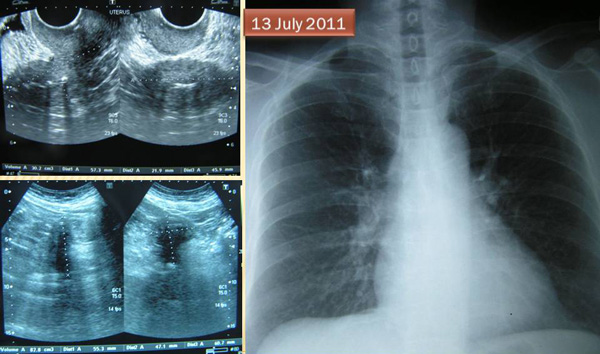

BH (S108) is a 65-year-old lady from Indonesia.  An ultrasound of her pelvis showed her cervix was enlarged with a focal bulge over the posterior part. This bulge or mass measures about 23 x 12 mm.

A chest X-ray on 13 July 2011 showed no significant abnormality see in the lungs and heart.

A biopsy was performed on 14 July 2011 and confirmed malignant cells infiltrating deep into the cervical parenchyma.  BH was referred to a cancer hospital for further management.

A CT scan was done on 18 July 2011. It showed a bulky uterine cervix measuring 4.9 x 3.7 cm with a hypodense lesion seen within.  This is in keeping with carcinoma of the cervix. No metastatic disease is evident in the abdomen.

BH underwent radiotherapy. She was told that there was a eighty-nine percent chance that she would be cured. BH had 25 sessions of external beam radiation and 3 sessions of brachytherapy (i.e. internal radiation).  In addition BH received 2 cycles of chemotherapy. All treatments were completed by 12 October 2011.